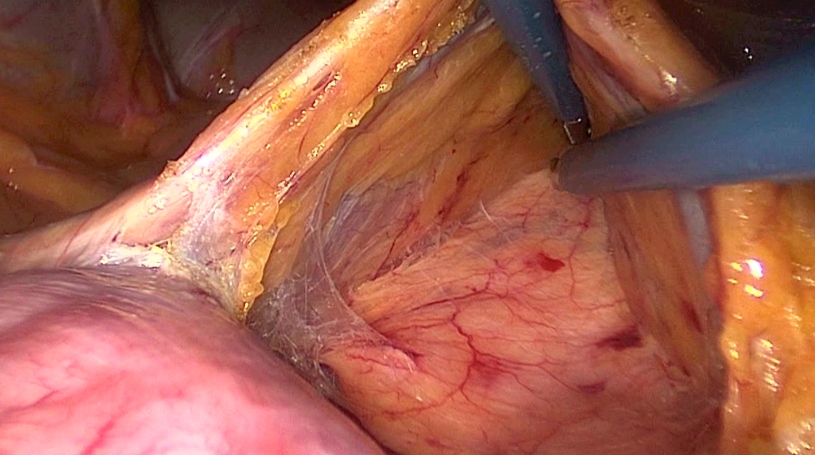

On the left/cephalad side of Gerota’s fascia care must be taken not to dissect under the pancreas. As a next step the VMI is divided close to the lower border of the pancreas after using clips for ligation or coagulation with a bipolar device.

Copyright Dr. Colin Sietses

Now at the upper border of the pancreas a small window is made through the mesentery to gain entry into the lesser sac. The stomach becomes visible. Both windows can now be connected leaving the transverse mesocolon intact and performing a dissecting on the surface of the pancreas.

For this disssection the fusion fascia as described by Toldt is divided. A thin layer of parietal peritoneum is left on the pancreas.

For this dissection the second assistent is lifting the mesocolon to show the bursa while the surgeon’s left hand is at the lower border of the pancreas.